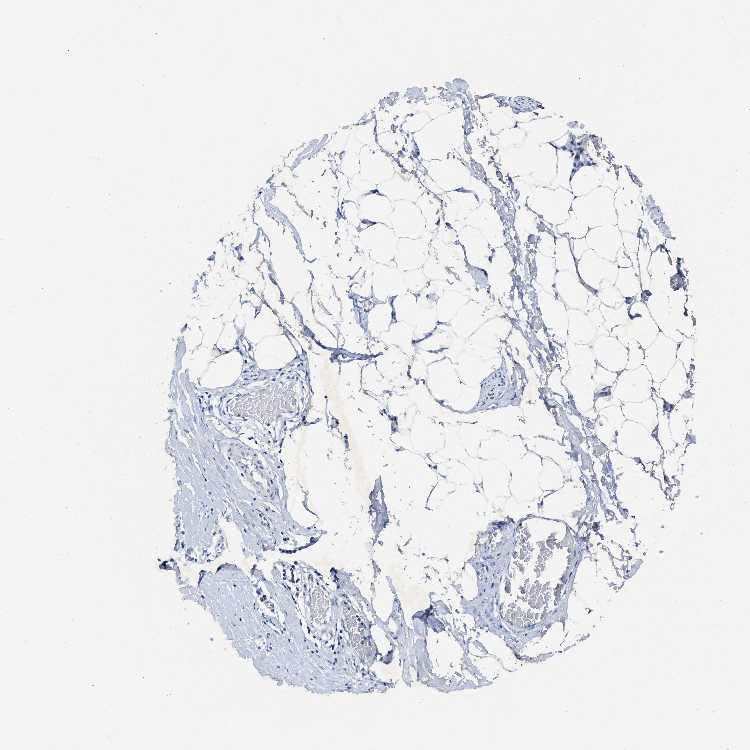

TISSUE PRIMARY DATA SOFT TISSUE Show tissue menu

SOFT TISSUE 1 - Antibody stainingi

Antibody staining in the annotated cell types in the current human tissue is reported as not detected, low, medium, or high, based on conventional immunohistochemistry profiling in selected tissues. This score is based on the combination of the staining intensity and fraction of stained cells.

Each image is clickable and will lead to virtual microscopy that enables deeper exploration of all samples and also displays staining intensity scores, fraction scores and subcellular localization as well as patient and tissue information for each sample.

Antibody HPA018331

Chondrocytes Not detected

Fibroblasts Not detected

Peripheral nerve Not detected

SOFT TISSUE 2 - Antibody stainingi